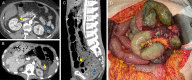

Background: Non-occlusive mesenteric ischemia (NOMI) is a life-threatening acute condition that has an overall in-hospital mortality rate of up to 75%. Critically ill patients are often admitted to intensive care units (ICUs) due to shock, and these patients are frequently at risk of developing NOMI. The objective of this study was to determine the clinical features of critically ill patients with NOMI and evaluate the risk factors for in-hospital mortality among these patients.

Methods: We reviewed the electronic medical records of 7,346 patients who underwent abdominal contrast-enhanced computed tomography during their ICU stay at Samsung Medical Center (Seoul, Korea) between January 1, 2010 and December 31, 2019. After reviewing each patient's computed tomography (CT) scans, 60 patients were diagnosed with NOMI and included in this analysis. The patients were divided into survivor (n = 23) and non-survivor (n = 37) groups according to the in-hospital mortality.